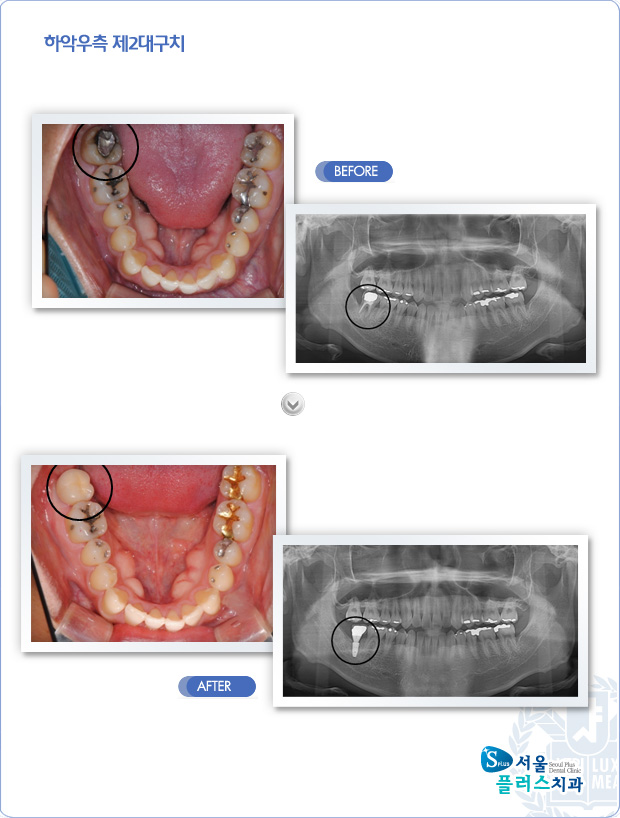

[임플란트] 하악우측 제2대구치